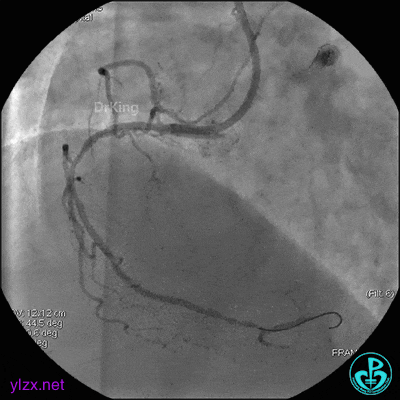

4 急诊冠脉造影

左主干轻度狭窄,左主干到前降支近端钙化影明显。前降支开口严重狭窄,近端闭塞。粗大回旋支轻度狭窄。

右冠脉无严重狭窄,右冠脉没有给前降支提供逆向供血。

EBU指引导管到位,导丝通过闭塞段到达前降支远端,经指引导管冠脉内推注替罗非班6ml,前降支恢复3级血流,闭塞段局部残余狭窄严重,2.0×15mm球囊扩张前降支近端闭塞处后再次冠脉内推注替罗非班8ml。下台继续治疗。